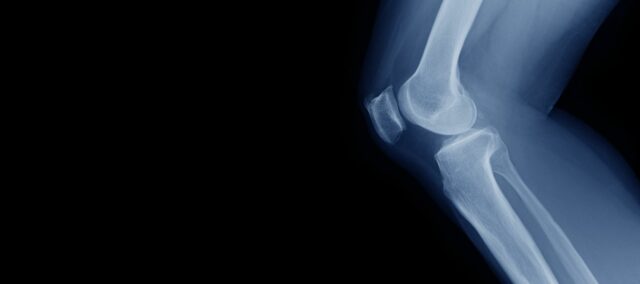

De invloed van quadricepssterkte op kniekraakbeen

Optimale quadriceps kracht is essentieel voor een goede kniefunctie in het dagelijks leven. Omdat de quadricepsspier een belangrijke stabilisator en schokdemper is, helpt hij de belasting op het gewrichtsoppervlak van de knie te verdelen. Dit is erg belangrijk, vooral in het licht van een vergrijzende bevolking en een toenemend aantal mensen met obesitas. Aangezien er momenteel geen echte behandeling is voor knieartrose (OA), is het cruciaal om de progressie naar OA te vertragen of - indien mogelijk - het ontstaan ervan te voorkomen. Daarom wordt versterking aanbevolen als eerstelijnsbehandeling voor knie-OA. Tot nu toe konden geen harde conclusies worden getrokken over de invloed van quadriceps kracht op kniekraakbeen. Dat is waar deze studie om de hoek komt kijken.